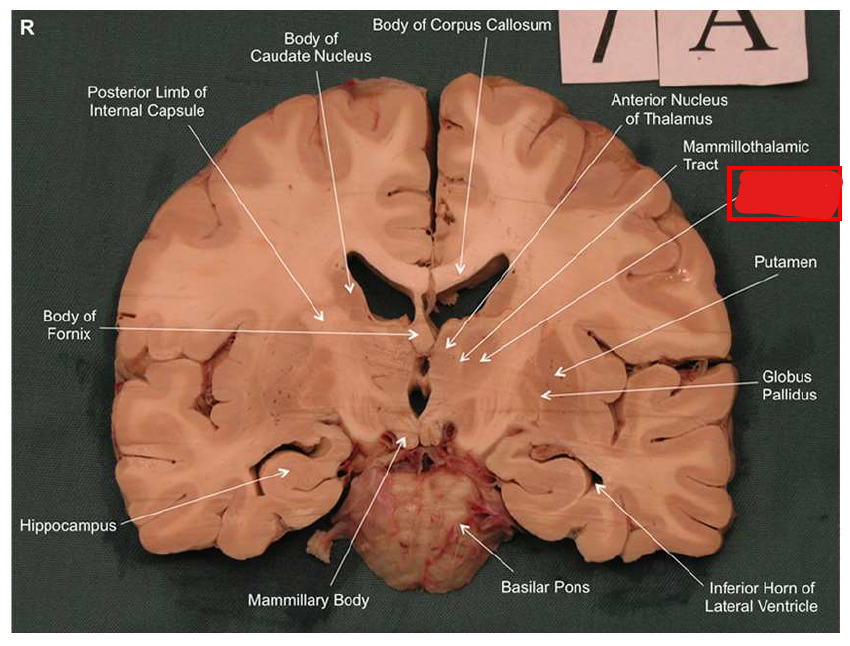

What is the fornix of the hippocampus?

Hippocampus output pathway (C-shaped)

Connects hippocampus to hypothalamus/mamillary bodies

Carries information to and from hippocampus

Important for memory consolidation and retrieval

What is this?

hippocampal fornix

How does the hippocampus form memories?

Association areas activate the hippocampus, which reverberates in the Papez circuit until information is stored permanently

Hippocampus → fornix → mamillary bodies → anterior thalamic nucleus → cingulate cortex → hypothalamus